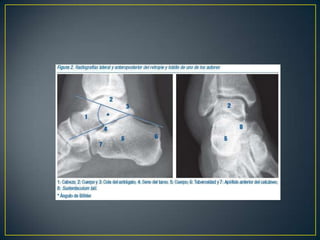

IIIIVVRADIOGRAFÍASSIMPLES 		    TOMOGRAFÍApreoperatoria

II  BTC  preoperatoriaIncongruencia subtalica  post.   :  90 %Conflicto maleolar externo            :  80 %Lesión calcáneo-cuboidea             :  40 %